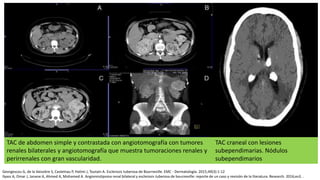

TAC de abdomen simple y contrastada con angiotomografía con tumores

renales bilaterales y angiotomografía que muestra tumoraciones renales y

perirrenales con gran vascularidad.

TAC craneal con lesiones

subependimarias. Nódulos

subependimarios